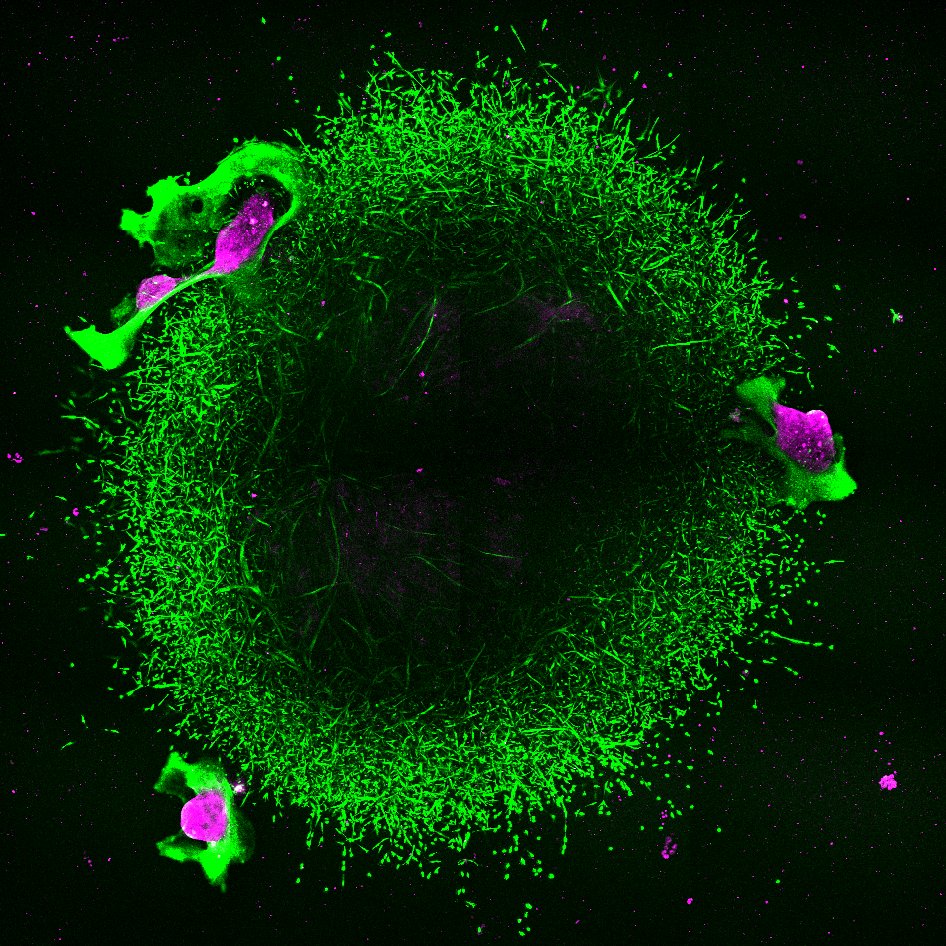

A dnes už vím, že některé vlastnosti nádoru mohou léčebnou účinnost nanočástic ovlivnit. Třeba nadměrný extracelulární matrix, tedy mimobuněčná hmota, která se nachází mezi buňkami tkání. V místě nádoru může tedy fungovat jako fyzická bariéra, která brání pronikání léčiva. Chci studovat, jak nanočástice s různými složkami nádorového mikroprostředí interagují. Projekt, na kterém teď pracuji, by měl identifikovat vlastnosti nanočástic, které umožní lepší průnik, a tím pádem účinnější distribuci léčiva. Věnuji se léčbě zaměřené přímo na extracelulární matrix a jeho hlavní producenty – fibroblasty.

Nejjednodušeji se nanočástice pozorují pomocí fluorescenčního značení. Pokud zbarvíme jejich povrch nebo vnitřek, můžeme sledovat jejich pohyb uvnitř buněk nebo uvnitř tkání laboratorních myší.

Co se týče vědecké práce, chci popsat, jak nanočástice interagují s mikroprostředím nádoru a popsat konkrétní vlastnosti, které by měly mít, aby se nezdržovaly ve fibrózním extracelulárním matrixu a mohly efektivně proniknout do nádoru a ničit tak rakovinné buňky. Případně zjistit, jakým způsobem modulovat extracelulární matrix. Tady v Melbourne mám k dispozici materiálovou expertizu a v Brně organoidní modely a pacientské tkáně, můžu to tak testovat přímo na nich, to je obrovský krok kupředu.